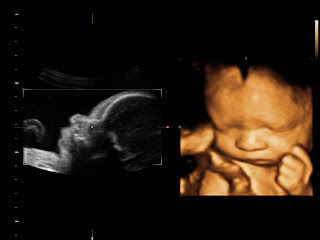

But today is what we are promised.  It is not up to me to know how many days the Lord has entrusted our sweet Seth into our care, but today I’m reveling in each and every kick, hearing his little swishing heart on the monitor and getting a peak at him often through ultra sounds.  I do not know what will be in store for his life, but I know he’s been a huge blessing and part of our family already.

Last Friday I had an ultrasound in our city and unfortunately we received some very tough news.  During the ultrasound they found fluid in the baby’s chest cavity surrounding the lungs and heart.  I knew it was a problem but didn’t quite know the words they were using to describe it, so after coming home and translating all the documents and talking with our doctor in Istanbul it was determined it is a clear case of fetal hydrothorax.  She was wonderful helping us figure out what was going on and locating places in Istanbul to help treat it.  However our company feels like it is a serious problem due to the amount of fluid our baby has on both side of his chest cavity.  Our amazing team of doctors and nurses afelt like the baby cannot get the care he needs in Istanbul and told us on Monday it’s best to go the states and seek out a good hospital in a large city with an excellent perinatology department with a good NICU.  We have made an appointment for this following Tuesday at KU Med in Kansas City.

The good thing is I got another sneak peak at Charge (we’ve adopted Calvin’s name suggestion for the time being until we decide on a name.)